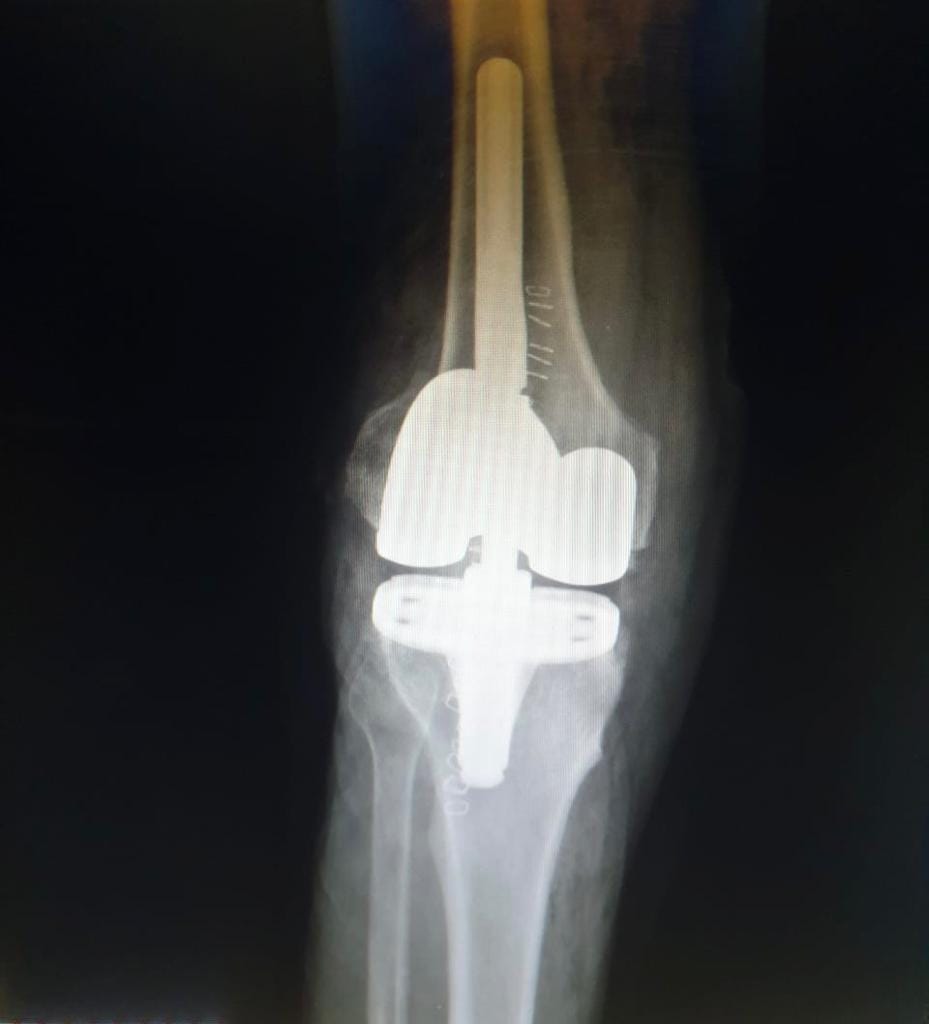

اجريت له العملية الجراحية

والمريض الان بحالة جيدة و الحمد لله.

وتألف الفريق الجراحي كلا من اخصائي جراحة العظام والكسور د. هادي عبدالله و د. فريد السوداني و د. يوسف علاء و اخصائي التخدير د قاسم عبدالله .